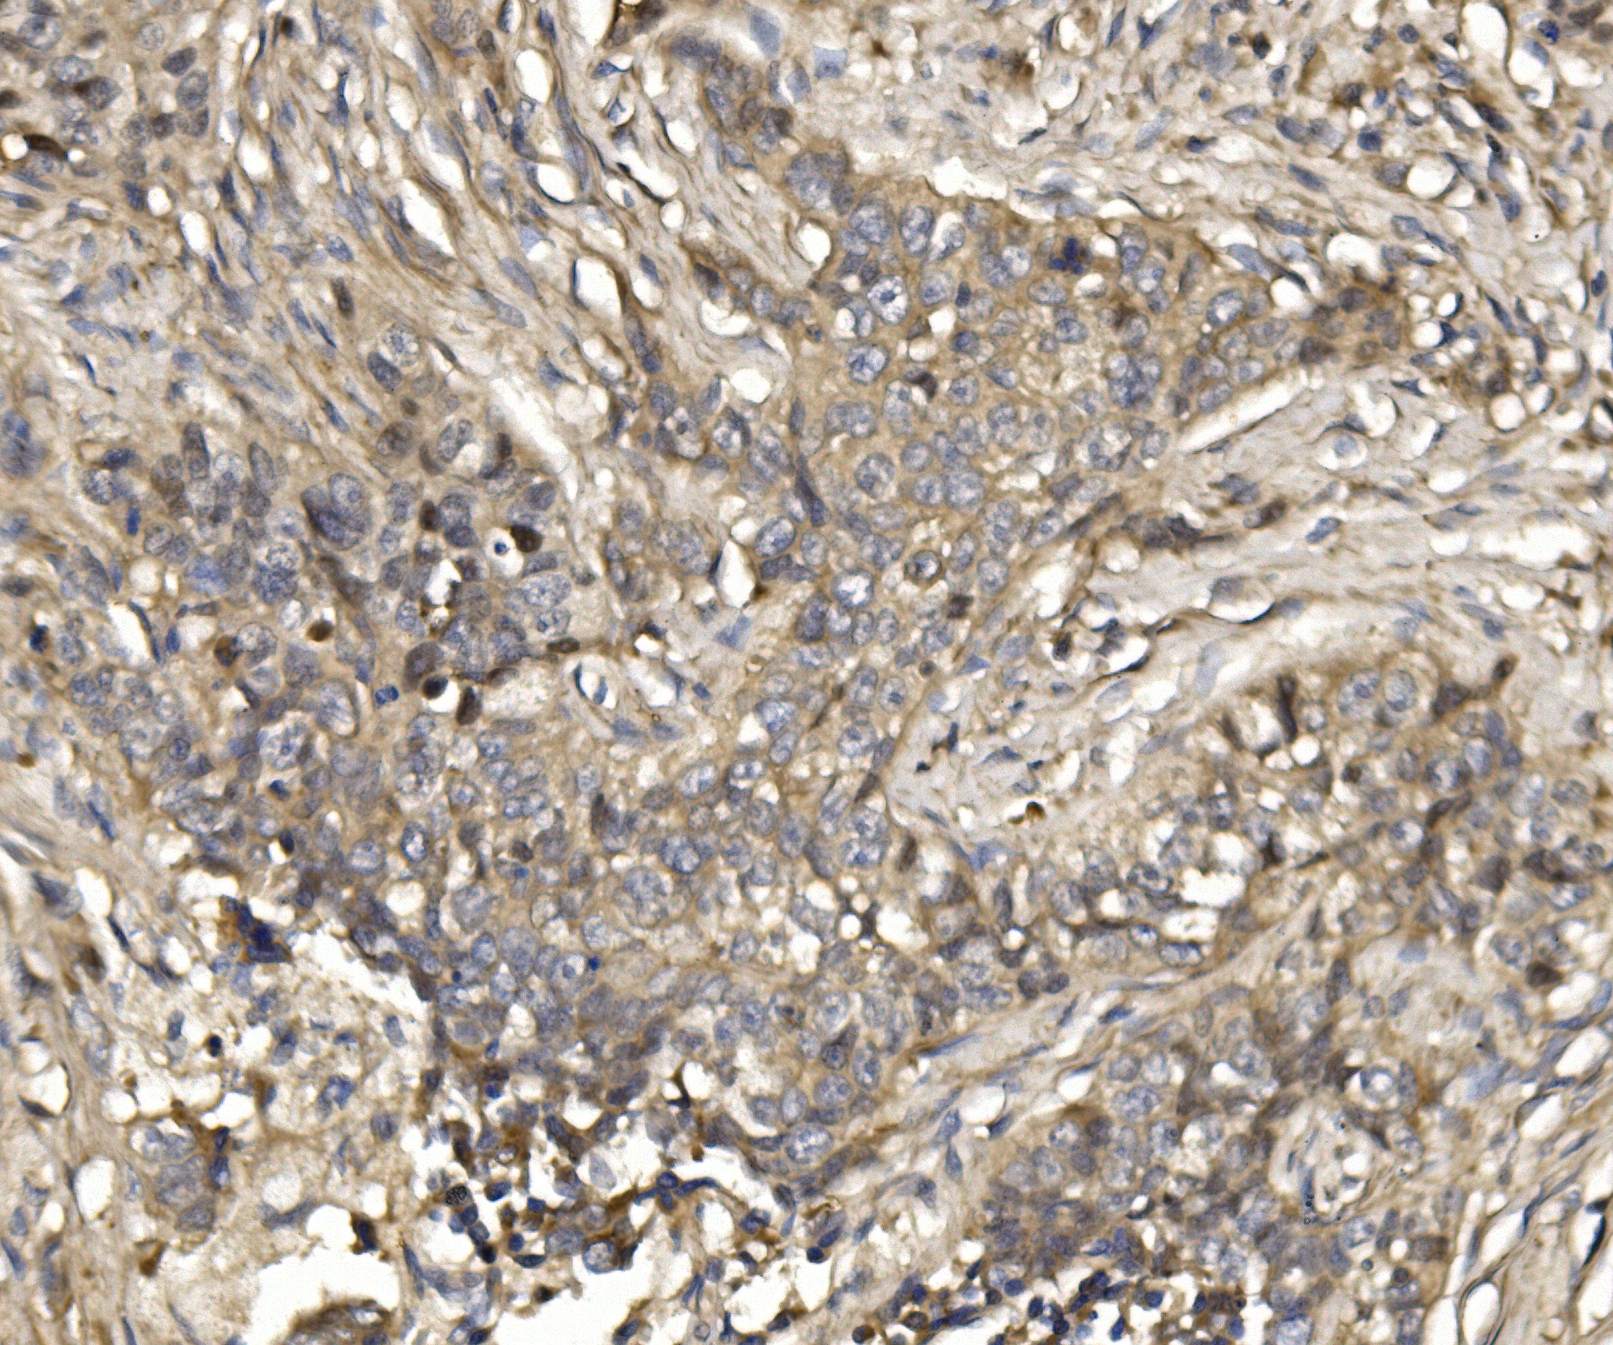

• IHC analysis of 14-3-3 Sigma/SFN using anti-14-3-3 Sigma/SFN antibody (BA3752).

14-3-3 Sigma/SFN was detected in a paraffin-embedded section of human intestinal cancer tissue. Biotinylated goat anti-rabbit IgG was used as secondary antibody. The tissue section was incubated with rabbit anti-14-3-3 Sigma/SFN Antibody (BA3752) at a dilution of 1:200 and developed using Strepavidin-Biotin-Complex (SABC) (Catalog # SA1022) with DAB (Catalog # AR1027) as the chromogen.